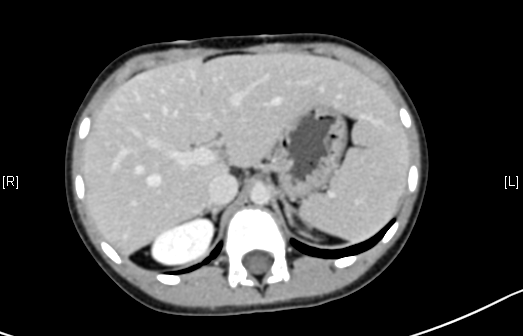

术前CT检查:

平衡期

腹部超声示:肝内包块。腹部CT:肝脏占位,血管瘤?上腹部增强CT:肝左内叶-右前叶交界区、尾叶囊实性团块影,考虑肿瘤(胆管囊腺瘤?间叶性错构瘤?)